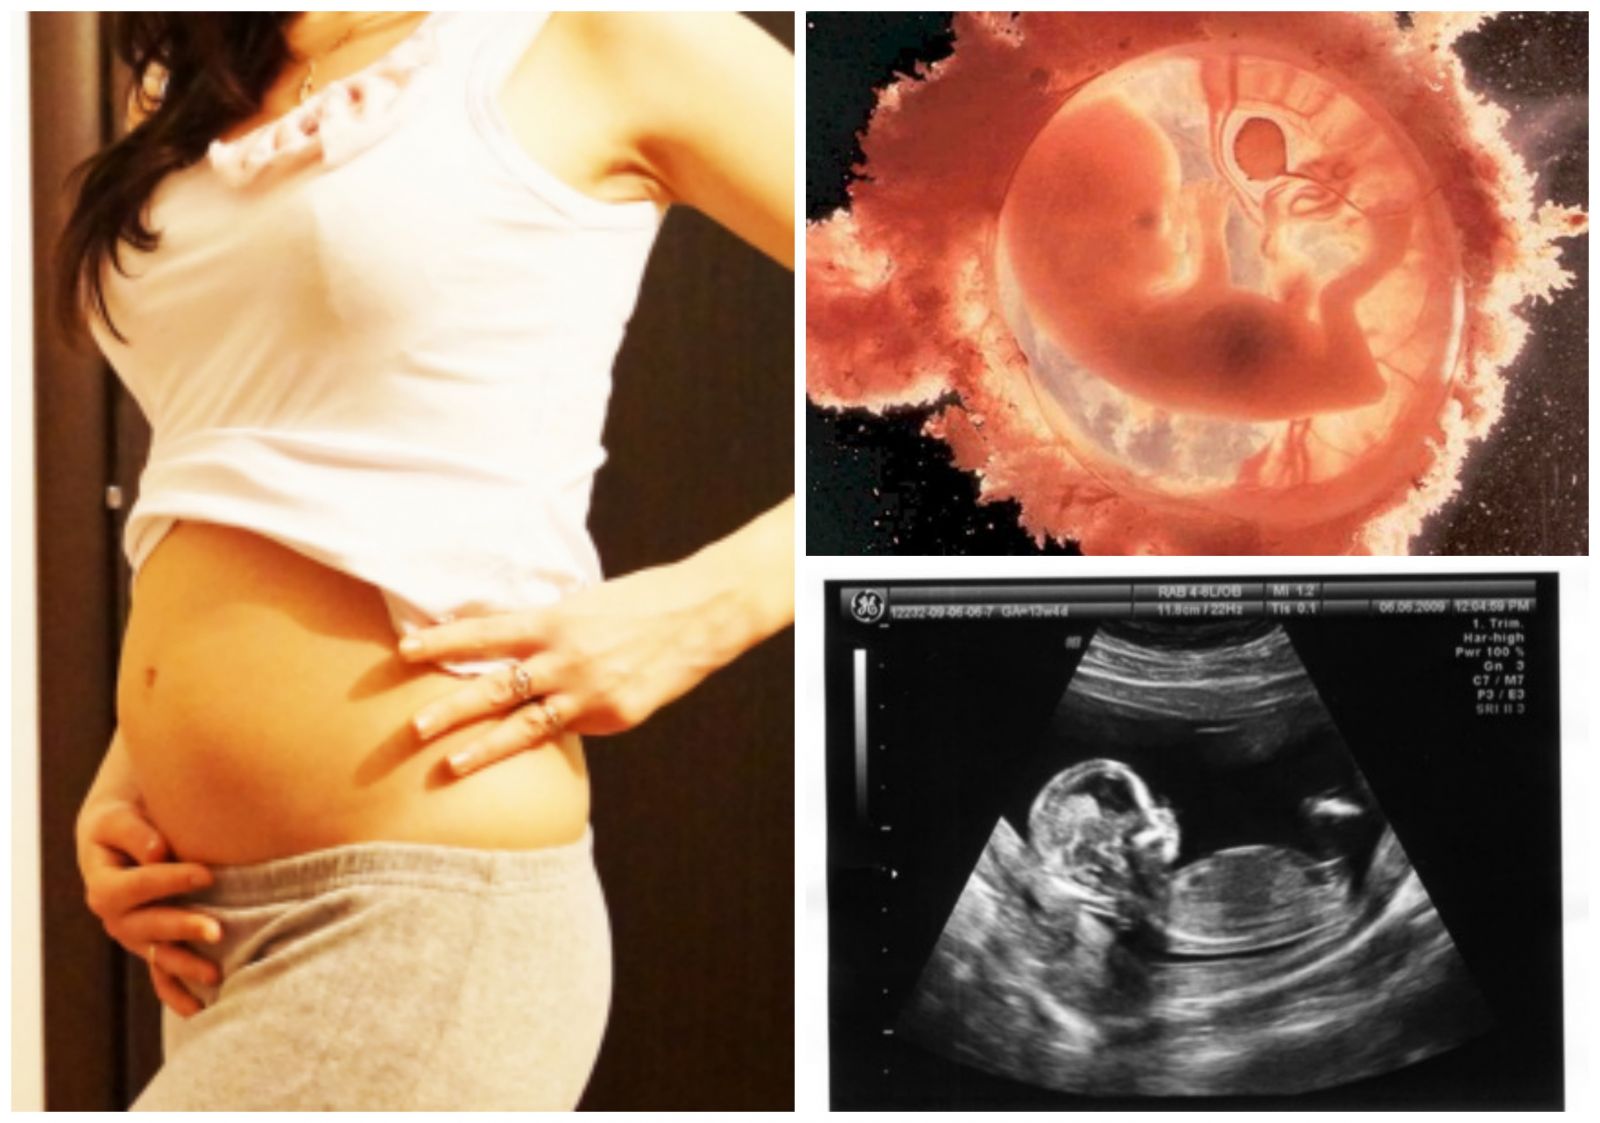

На 13-й неделе беременности плод продолжает активно развиваться, и врачи отмечают, что в этот период формируются важные системы организма. Размеры плода достигают около 7-8 см, а его вес составляет примерно 20-25 граммов. Врачи подчеркивают, что на этом этапе уже можно различить основные черты лица, а также начинают развиваться конечности. Сердце плода уже полностью сформировано и активно перекачивает кровь.

| 13 | Размер: Около 7-8 см от макушки до крестца. Вес: Примерно 20-25 грамм. Органы: Все основные органы сформированы и начинают функционировать. Кости: Кости становятся более твердыми. Лицо: Черты лица становятся более выраженными, глаза перемещаются ближе к центру. Движения: Плод активно двигается, но мама пока не чувствует этих движений. Рефлексы: Развиваются сосательный и глотательный рефлексы. | Изображение плода, похожего на маленького человечка, с хорошо различимыми конечностями и чертами лица. |

На 13-й неделе беременности внутри вас происходят важные изменения: ваш малыш уже достиг размера персика, его длина составляет почти 6 см, а вес — около 13 граммов. При следующем ультразвуковом исследовании вы сможете заметить, что голова ребенка все еще пропорционально меньше его тела, которое стремительно растет.

Глаза вашего ребенка уже сформированы, но веки пока закрыты, чтобы защитить их. Уши находятся на своем месте, а голосовые связки малыша теперь тоже развиты. Если повезет, вы сможете увидеть, как он сосет большой палец во время ультразвукового обследования.

Ниже представлены фотографии развития плода на 13-й неделе беременности: